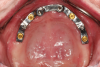

A bead line is scribed on the palatal section to create a seal of the framework to the tissues and the major connector is designed to cover as much of the hard palate as the patient will permit. A finish line is placed on the palatal portion of the major connector and two to four tissue stops are placed in the relieved retentive mesh of the framework to aid in processing the acrylic resin. The framework is exported from the design software and produced using metal additive manufacturing techniques or a combination of additive manufacturing and casting (Figure 9). The framework is evaluated intraorally and typically in combination with denture teeth to assess occlusal vertical dimension, centric, phonetics, and esthetics prior to processing. The prosthesis is completed using conventional acrylic resin processing techniques.

Fig 9. Completed maxillary framework is 3D

printed by an industrial laboratory (Bertram

Dental in Menasha, Wisconsin).

Figure 9